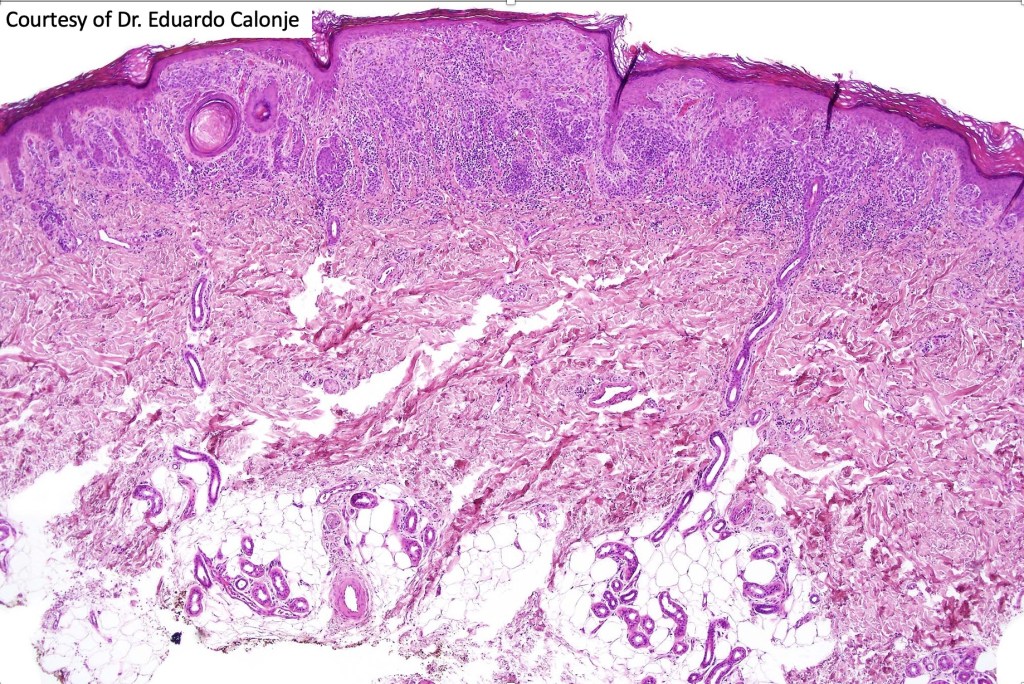

Combined common & deep penetrating nevus